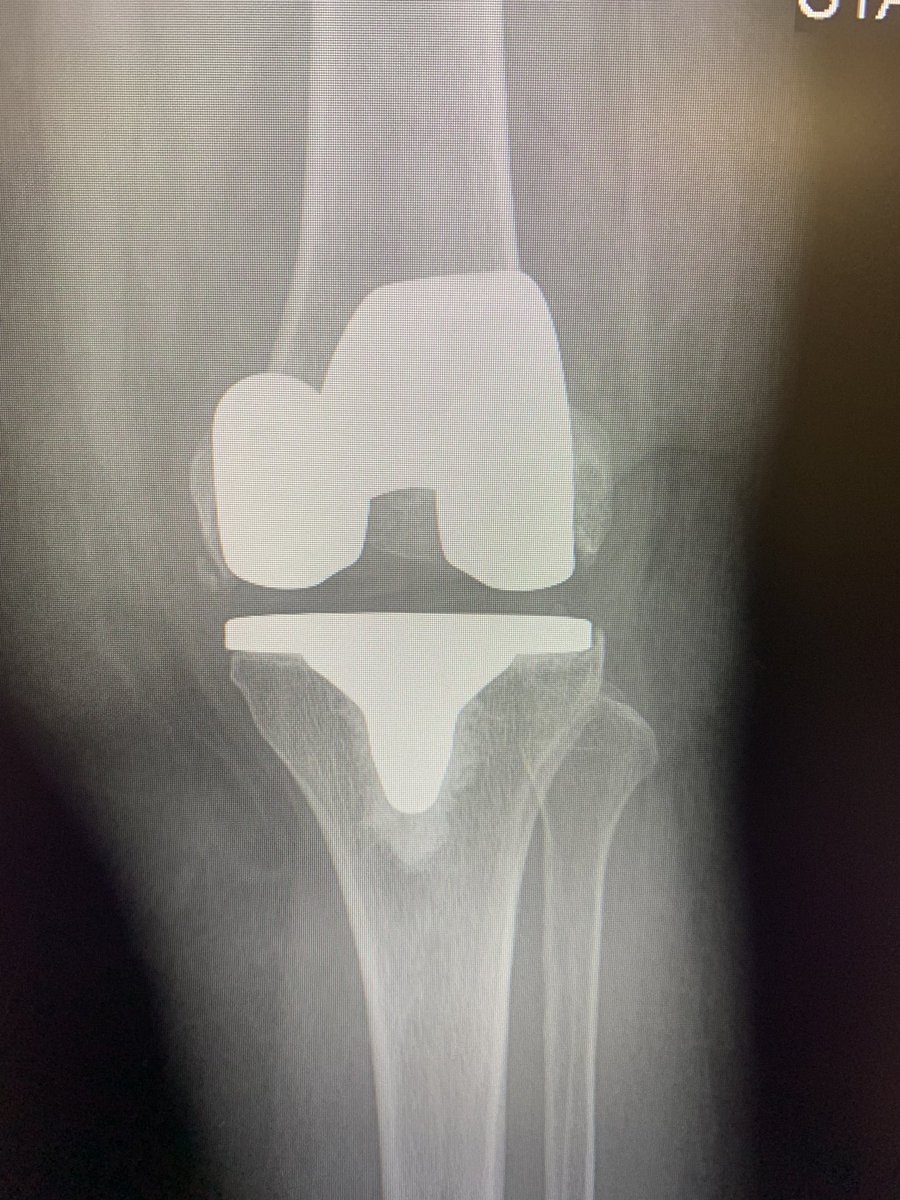

One of my favorite parts of navigation is very accurate control of tibial slope. What are your preferred uses ? Work around hardware? Coronal plane alignment? @intellijoint @DeviceNation #orthotwitter

3